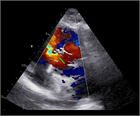

心室中隔欠損症(Ventricular Septal Defect, VSD)

1. 成人循環器内科医が診るVSDのほとんどは小欠損孔のrestrictive VSDとなる。なかにはsmall-moderate size(小~中欠損孔)restrictive VSDで小児期には血行動態的に影響がなかったが、成人期に心室コンプライアンス低下や体血管抵抗の上昇により左→右シャントが増加して左室拡大をきたすことがある。

1. 必要な検査と所見:身体所見、心エコー

1. 大動脈弁閉鎖不全症、肺高血圧合併例は専門施設への紹介を検討する。